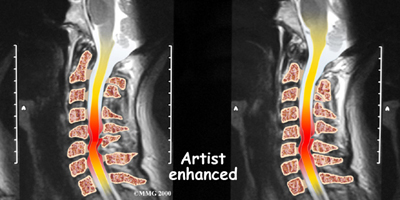

Magnetic resonance imaging (MRI)

If more information is needed, your doctor may order an MRI. The MRI machine uses magnetic waves rather than x-rays to create pictures of the cervical spine in slices. MRIs show the cervical spine vertebrae, as well as the soft tissue structures, such as the discs, joints, and nerves. MRI scans are painless and don't require needles or dye. MRI scan has become the most common test to look at the cervical spine after x-rays have been taken.